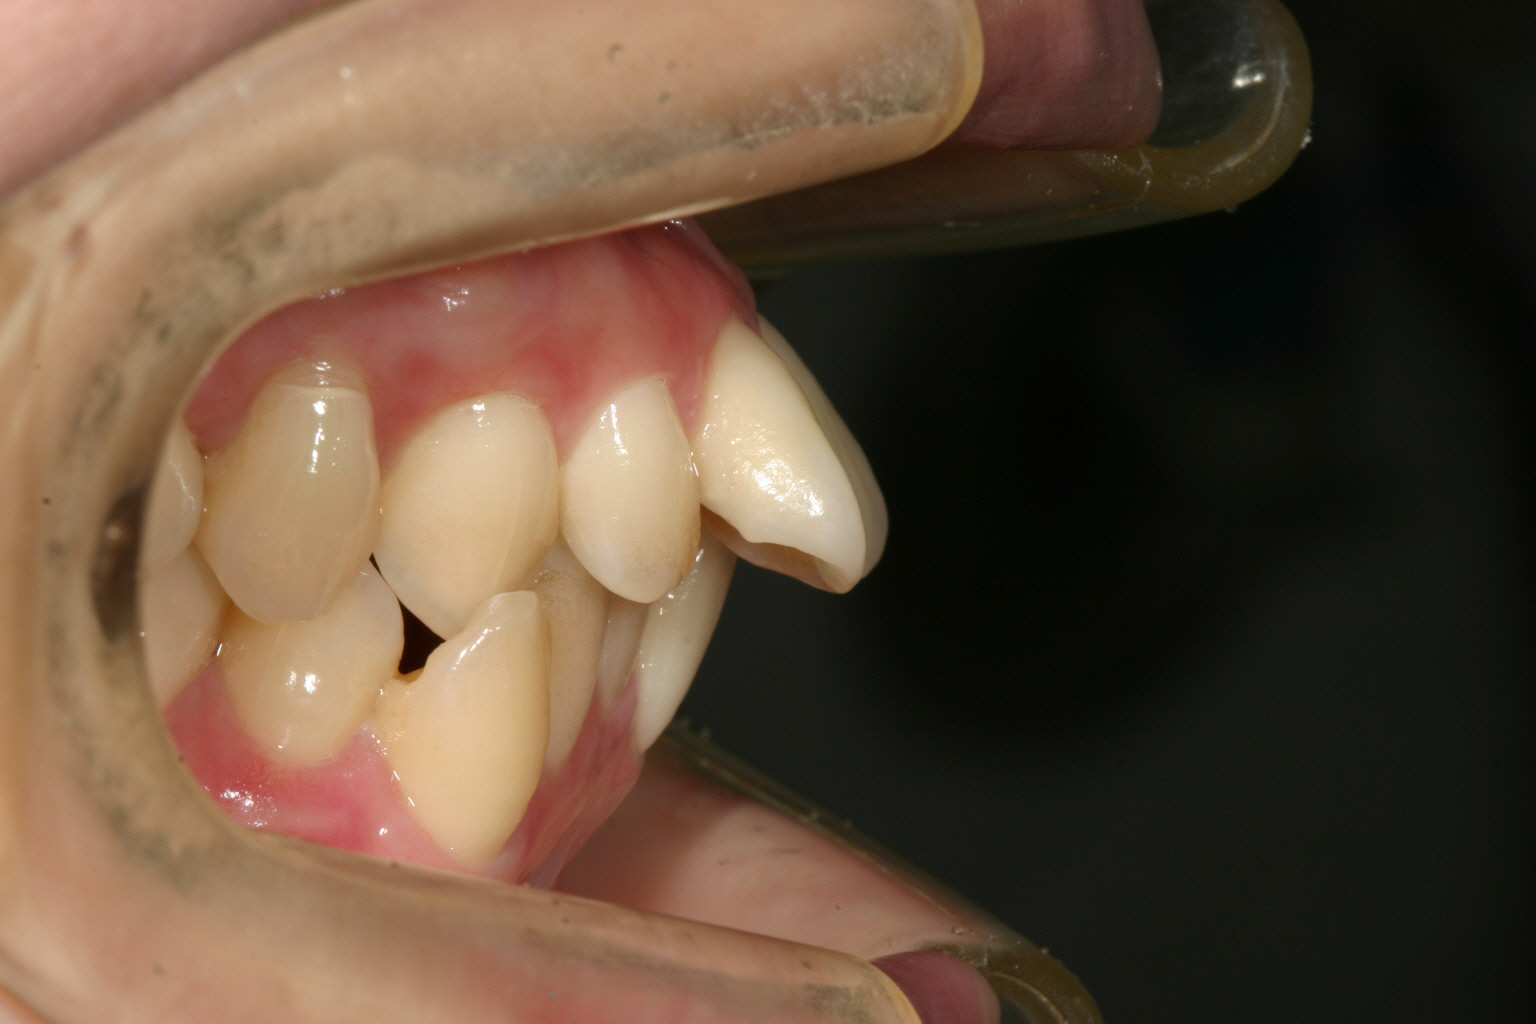

でっ歯が反り返って唇に当たって痛い。

かなりヘビーな翼状捻転です。

出っ歯観が患者様が一番気になるところです。

やはりこれだけ歯が出てますと見た目も違和感も大きく又何かに口をぶつけた時も唇切れたりや前歯の破折等も伴いますので早い目の処置をお薦め致します。